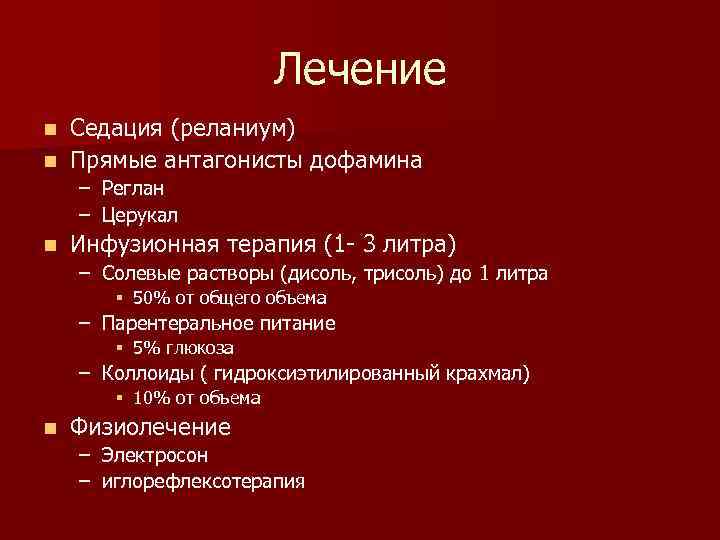

Лечение Седация (реланиум) n Прямые антагонисты дофамина n – Реглан – Церукал n Инфузионная терапия (1 - 3 литра) – Солевые растворы (дисоль, трисоль) до 1 литра § 50% от общего объема – Парентеральное питание § 5% глюкоза – Коллоиды ( гидроксиэтилированный крахмал) § 10% от объема n Физиолечение – Электросон – иглорефлексотерапия

Лечение Седация (реланиум) n Прямые антагонисты дофамина n – Реглан – Церукал n Инфузионная терапия (1 - 3 литра) – Солевые растворы (дисоль, трисоль) до 1 литра § 50% от общего объема – Парентеральное питание § 5% глюкоза – Коллоиды ( гидроксиэтилированный крахмал) § 10% от объема n Физиолечение – Электросон – иглорефлексотерапия